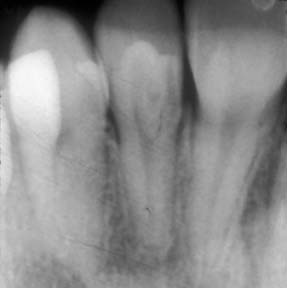

We follow the American Academy of Dentistry and American Academy of Pediatric Dentistry guidelines for taking dental X-Rays. Dental x-rays will be taken as needed during their routine cleaning appointments to check for cavities in between their teeth, survey erupting teeth, diagnose bone disease, evaluate the results of an injury, or plan orthodontic treatment. We will always minimize your child’s radiation exposure by prescribing X-Rays on an individual basis which depends on your child’s individual risk factors for oral disease. Your child will also wear a lead body apron during the process. If you have any concerns about X-Rays for your child, please discuss them with our staff.

A cavity that involves the nerve (pulp) of the tooth may cause a child to experience intense pain. Although the pain may subside for a period of time using ibuprofen or antibiotics, it will return unless the tooth is properly treated. When the nerve of the tooth is infected, it must be treated to restore the child to good dental health.

A pediatric root canal procedure is referred to as a “pulpotomy.” The purpose of root canal treatment is to maintain the vitality of the affected tooth so that the tooth will not be lost early. Early loss of posterior (back) primary teeth may cause future problems with the eruption of permanent teeth. Therefore, it is best to avoid early loss of primary molars by properly treating the nerve of infected teeth with a pulpotomy. Dental caries (cavities) and traumatic injury are the main reasons for a tooth to require pulp therapy. The pulpotomy root canal procedure removes the infected pulp tissue within the crown of the tooth. A medication is placed to calm the nerve of the tooth and prevent bacterial growth. The pulpotomy is followed with a final restoration of a stainless-steel crown.

After the pulpotomy (root canal procedure) is complete; your child should feel much better. We expect all pain to subside either immediately or within a few days of the procedure.